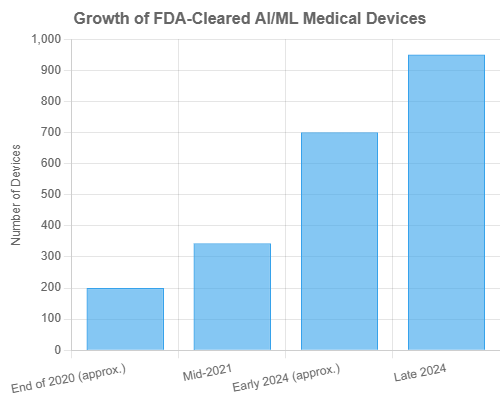

The integration of AI into medical equipment has seen exponential growth, marked by an increasing number of regulatory approvals and a burgeoning market. The U.S. Food and Drug Administration (FDA) has been actively involved in this space. As of October 2024, the FDA had cleared or approved 950 medical devices incorporating AI/ML, a significant leap underscoring the technology’s maturation and clinical validation (Nature, Oct 3, 2024). This represents a steep increase over the past decade, with imaging applications initially dominating the field, though AI is now expanding into various other medical specialties (MedTech Dive, Oct 9, 2024).